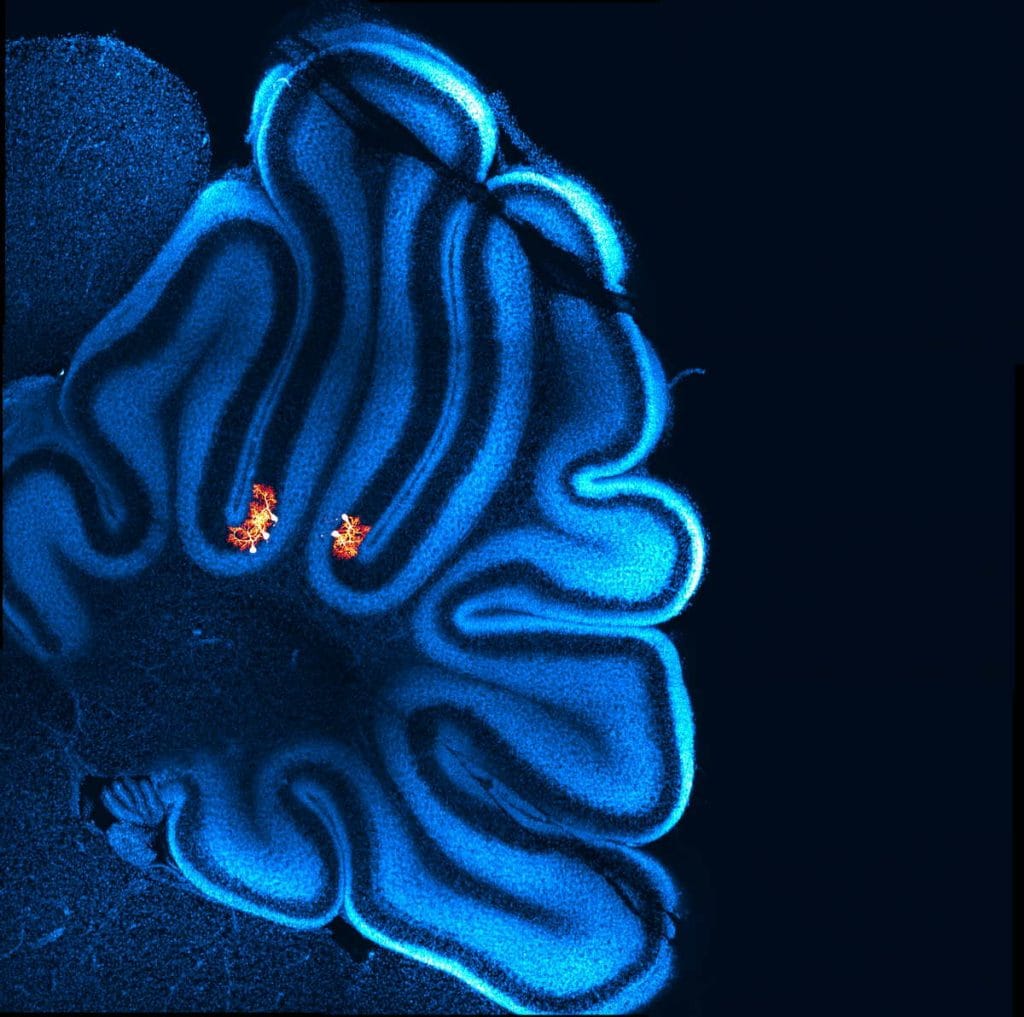

The outermost layer is the cortex—a thick sheet of neural tissue, highly folded and cramped within the skull. This layer, often found to be comparatively dense in humans, has traditionally been associated with higher-level functions such as intelligence, language, perception, and decision-making. For long, it has been seen as the “special ingredient” of the human brain.

As we keep peeling back the layers, deeper within the brain lies the hippocampus. Due to its deep-seated location, performing invasive studies and examining live hippocampal tissue has been particularly difficult in humans.

Jonas Lab’s focus has been on one area in particular: the CA3 region of the hippocampus. It’s a key auto-associative network, meaning it binds together otherwise unrelated information into one memory. A rainy afternoon, for instance, might be remembered as the smell of something cooking, your favourite song playing, grey clouds outside.

Shaped like a seahorse, the hippocampus has several subregions—CA1, CA2, CA3 and CA4—connected in sequence, like stations on a train line. The full significance of the hippocampus wasn’t known until 1953, when a 27-year-old man known as HM underwent experimental surgery for severe epilepsy. Doctors removed most of his hippocampus. The procedure controlled his epilepsy, but left him unable to form new memories. He lived for 55 years thinking he was 27, existing in a kind of permanent present. HM’s case became a turning point in neuroscience and established the hippocampus’s indispensable role in our grasp on memory.

When the Jonas lab team examined the CA3 region of the human hippocampus, they discovered something unexpected. The neurons were farther apart and had fewer connections than in mice. That’s the opposite of what they saw in areas like the cortex, where human neurons typically exhibit more connections than their mouse counterparts.

“Why on earth have we got this sort of opposite scaling?” Watson recalled exclaiming. The lab ran mathematical models and hypothesised that this sparser wiring might give humans “optimized memory storage capacity,” as Watson, Peter Jonas, and other researchers wrote in a Cell paper published in January this year.